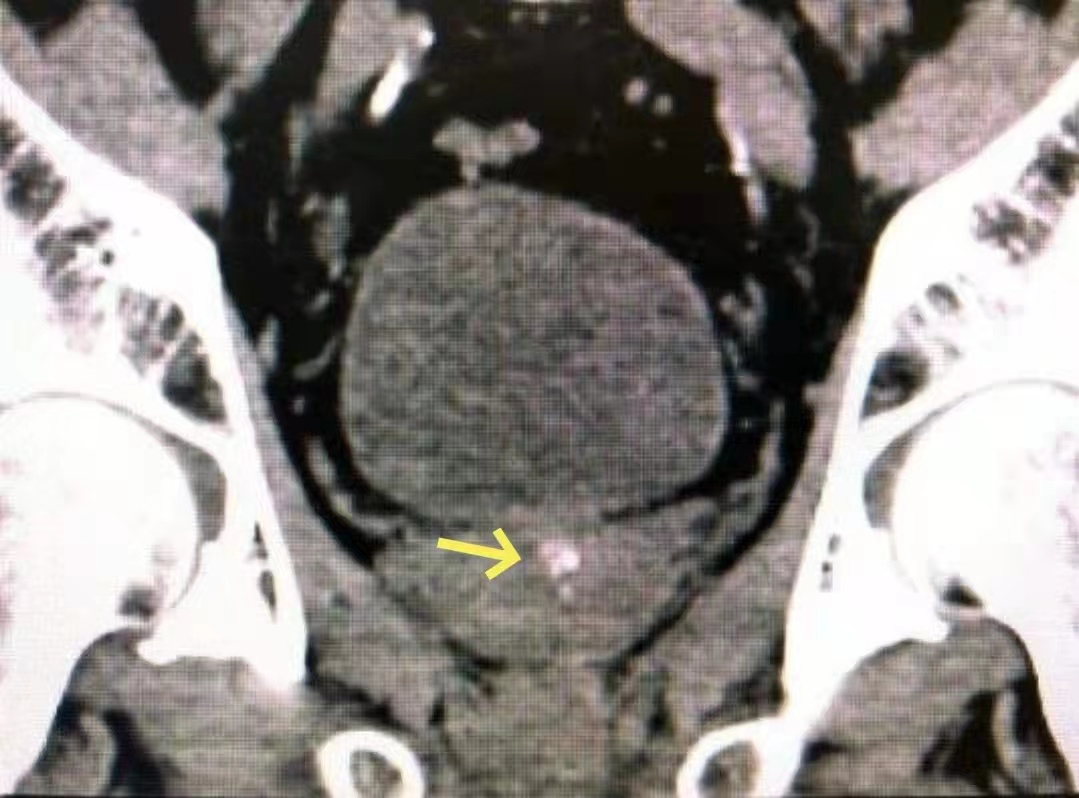

是的,CT是这样的↓

b膀胱镜为什么消毒泌尿外科迈向微创时代新“镜”界——膀胱镜_https://www.jmylbn.com_新闻资讯_第7张

CT也能看到结节,还能看到膀胱周围组织的情况,但是还是不能确定结节的性质。

那么问题来了,患者是前列腺增生合并前列腺结石(钙化)还是前列腺部的尿道结石嵌顿呢?

彩超和CT都不很明确,无法对这两种疾病进行准确的鉴别。恰恰这两种疾病的治疗方式也完全不同,让临床医生也很头疼。